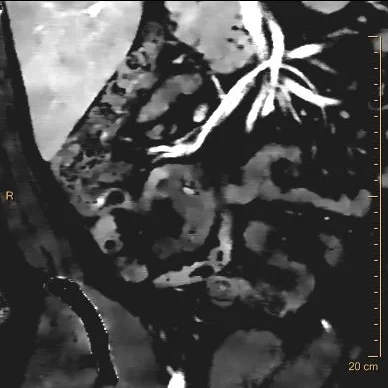

38 year old male presents to the ER for abdominal pain for the last 24 hours. WBC count was 9.77 k/cmm. CT scan was performed, shows clear acute appendicitis. Patient was taken to the OR, where appendicitis was confirmed. There was purulent fluid around the appendix.

So can we diagnose perforation on CT?

This paper from Philadelphia, published in 2003, talks about discontinuous enhancement as a very good sign of appendiceal perforation on CT. Over the years, I have found it very accurate. But it is a sign that takes experience to recognize, and may be difficult to get residents to appreciate. And spectral CT, of course, can help!

Going back to the CT scan on our patient, note the base of the appendix is normal, and there is a lot of inflammation around the middle of the appendix, where there is a small appendicolith. There is markedly decreased iodine uptake in the wall, and on the iodine map, there is no uptake where the normal wall should be. This is a clearly perforated appendix!

Path report : "Pink-tan to hemorrhagic and rough with an area of perforation in the middle appendix."

Conventional CT: Note obviously inflammed mid-appendix with small lith.